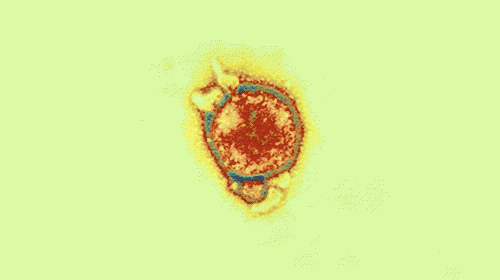

看看,这是病毒在干死细胞的作案现场。